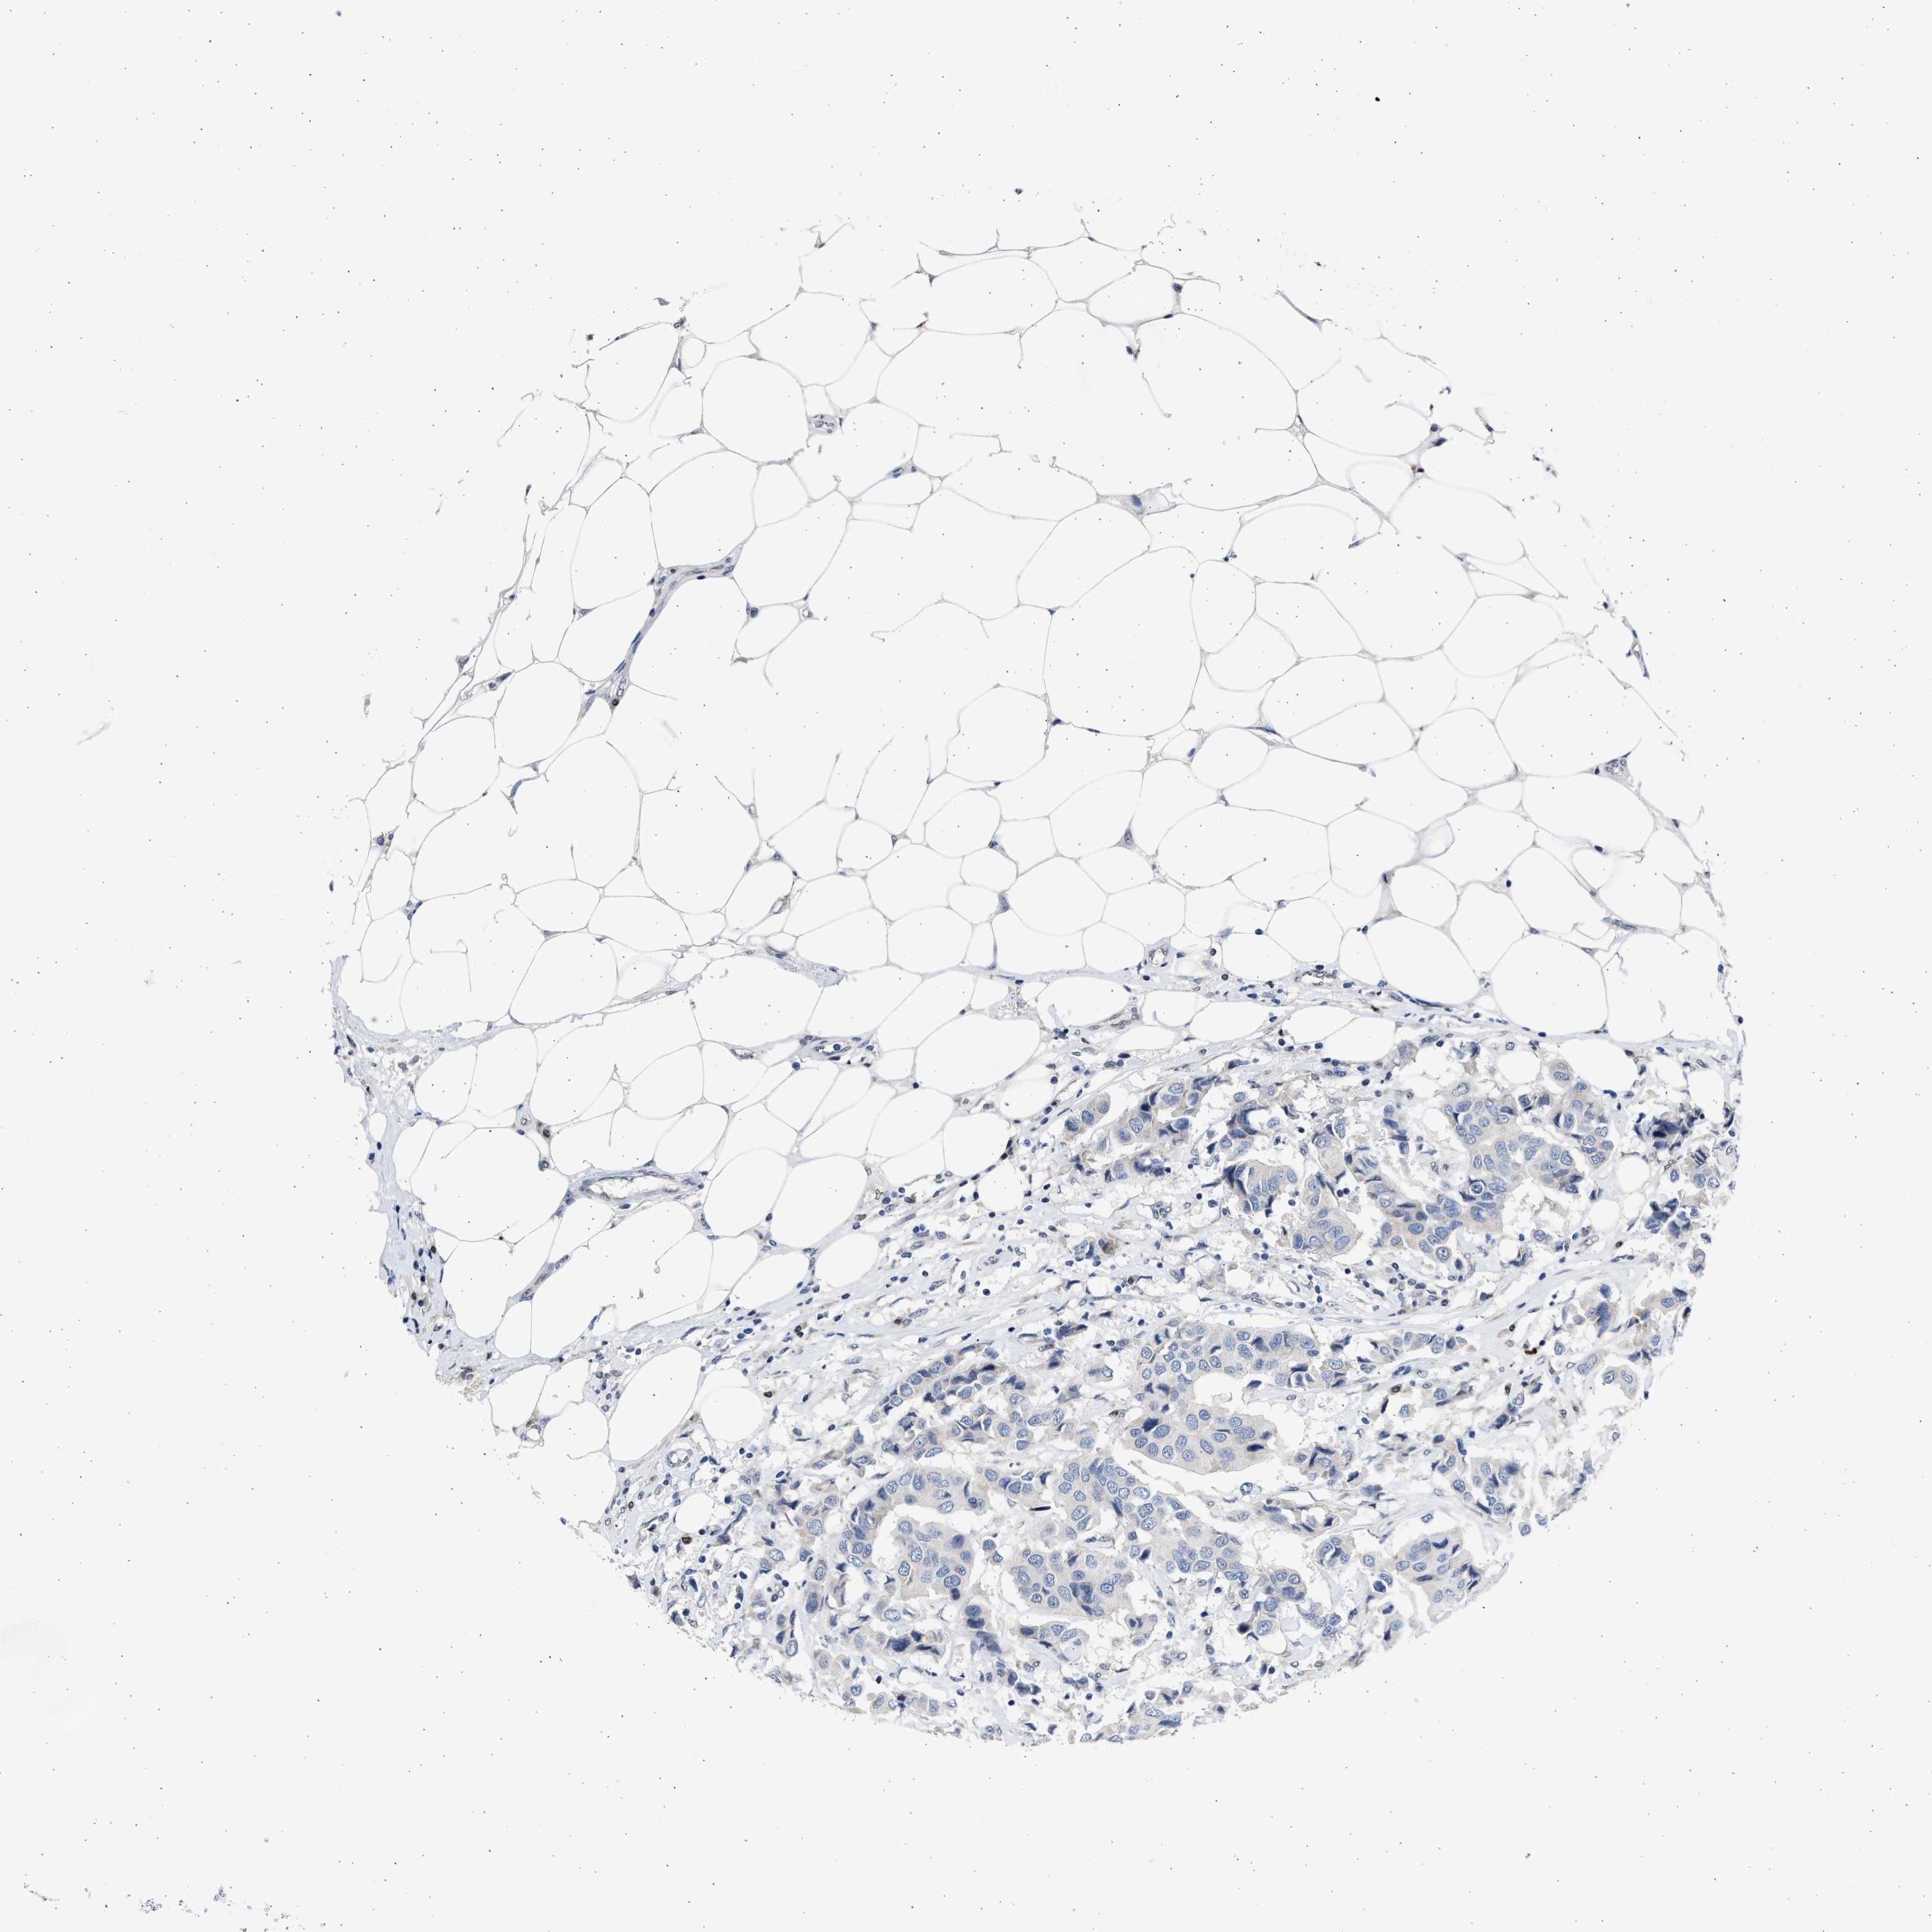

CANCER BREAST CANCER Show tissue menu

BRCA TCGA BRCA VALIDATION PROTEIN EXPRESSION

ANTIBODIES

AND

VALIDATION